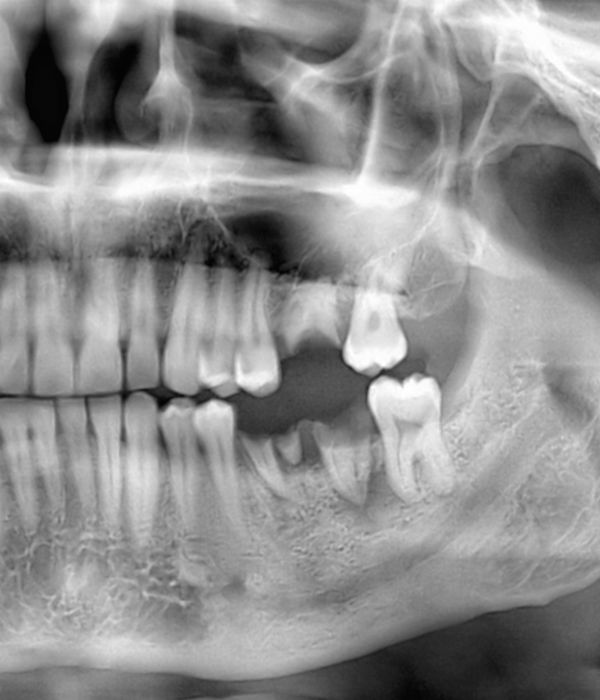

Bone Grafting

During bone grafting, our surgeons will replace lost tissue and rebuild your jaw structure. We will typically use a sample of your own bone, taken from your hard palate or another part of your body, or a synthetic material. The new tissue will strengthen the jaw, forming a solid base for implants.